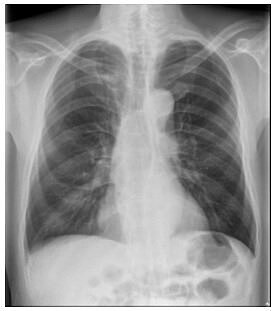

醫師洪盈盈說明,62歲上班族男子接受胸部X光檢查,未顯示肺癌。圖/洪盈盈提供

澄清醫院柏忕健康管理中心醫學影像科醫師洪盈盈說明,胸部X光敏感度有所限制,有時候1.5公分的腫瘤也不一定看得到。

洪盈盈指出,一般民眾的迷思認為「定期胸部X光檢查,就可以發現早期肺癌」,事實上,「1公分以下的肺部腫瘤很難發現」。有時候,1.5公分的腫瘤也不一定看得到,此個案就是很典型的例子。因為很多肺癌早期生長時密度很低,呈現出來的毛玻璃影像看起來淡淡的,也有可能藏在胸椎、心臟、肋骨、橫膈膜或肝臟前後方,這些皆是X光影像的死角。